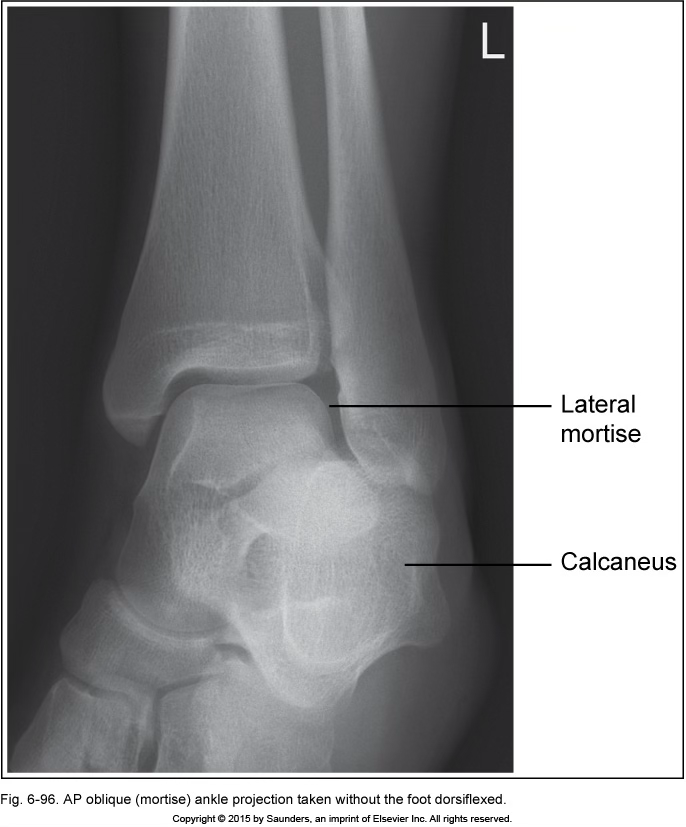

AP oblique ankle (mortise)

foot not dorsiflexed